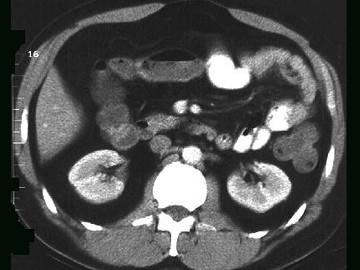

问题 女,30岁,右下腹痛,腹泻便秘交替出现,消瘦乏力,血沉加快,X线检查如图,最佳的诊断是 ( )

选项 A、结肠癌 B、阑尾炎 C、小肠结核 D、小肠克罗恩病 E、小肠癌

答案 D